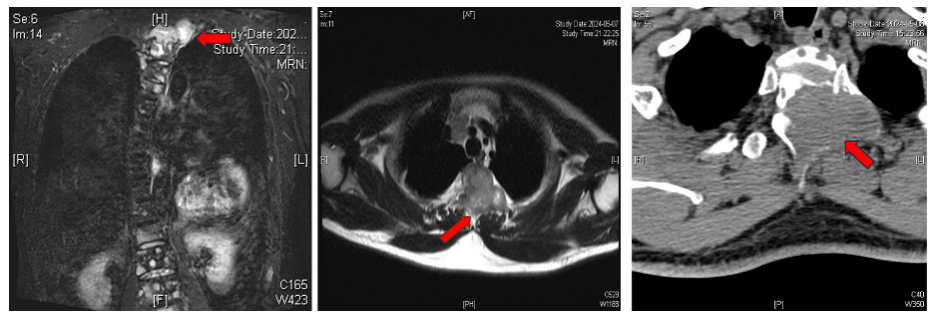

徐杨主任医师团队迅速为其安排磁共振、全身骨扫描(ECT)和PET-CT等检查。发现患者下肢瘫痪是因为第1-2胸椎肿瘤压迫脊髓导致的,而且全身其他多处骨质也被转移破坏了,考虑是胸腺癌多发转移。

多个检查考虑患者癌转移,红色箭头为肿瘤位置